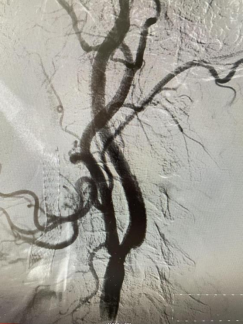

患者是一位古稀老人,已飽受高血壓病困擾,1月前行頭頸血管檢查可見雙側(cè)頸內(nèi)動脈狹窄80%以上,其發(fā)生中風(fēng)風(fēng)險極高?;颊呒覍僬业缴窠?jīng)內(nèi)科尋求進一步診治。因為患者高齡,雙側(cè)頸動脈嚴重狹窄,無頸動脈內(nèi)膜剝脫術(shù)(CEA)指征,科室團隊討論后決定為其行頸動脈支架植入術(shù)(CAS)。對于介入治療,該患者也面臨同期或分期完成雙側(cè)頸動脈支架植入治療的選擇。分期雙側(cè)頸動脈支架植入有增加病人痛苦、住院時間長和費用增加的缺點,以及術(shù)中、術(shù)后低灌注引起未治療側(cè)腦梗死,術(shù)后高灌注造成治療側(cè)腦出血等風(fēng)險。同期雙側(cè)頸動脈支架植入術(shù)增加手術(shù)操作的時間和難度,雙側(cè)頸動脈狹窄同時解除會使顱內(nèi)血流迅速增加,與分期手術(shù)相比,可能會增加潛在的高灌注綜合征發(fā)生的風(fēng)險,同時刺激雙側(cè)頸動脈竇壓力感受器,可能會導(dǎo)致更嚴重、持久的血流動力抑制,甚至心跳驟停。通過與家屬積極溝通,科室團隊充分討論后,決定采用同期雙側(cè)頸內(nèi)動脈支架植入術(shù)治療方案??剖覉F隊完善術(shù)前準備,制定各項手術(shù)應(yīng)急預(yù)案和措施,手術(shù)順利。術(shù)后科室團隊密切監(jiān)護患者生命體征,無神經(jīng)功能缺損癥狀出現(xiàn),現(xiàn)患者痊愈出院。

(右側(cè)頸內(nèi)動脈治療后) (左側(cè)頸內(nèi)動脈治療后)